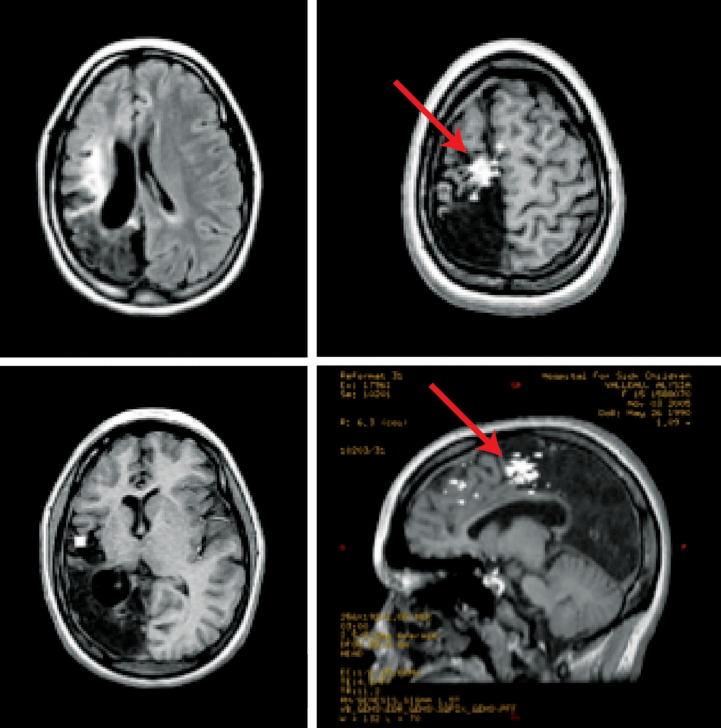

左軸向MR顯示廣泛的腦軟化;右側(cè)軸位和矢狀位MR顯示在外傷性腦軟化和正常的Rolandic皮質(zhì)交界處的有一個穗簇(紅色箭頭)

患者是一名12歲女孩,患有頑固性癲癇,她曾在嬰兒時期遭受過創(chuàng)傷性腦損傷,導(dǎo)致右側(cè)頂枕葉明顯的腦軟化。在接受了影像引導(dǎo)下的MEG穗簇切除后,她的癲癇未再發(fā)作,生活變得前所未有的平靜。對于難治性癲癇,Rutka教授會為其定制治療方案,盡可能在確定效果的前提下減輕患者的痛苦。